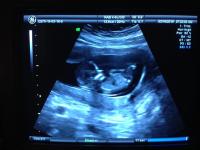

Csajok tul vagyok a 12.heti uh-n!Minden adat rendben.Jelenleg a popsijatok a feje bubjaig 64 mm :oops: